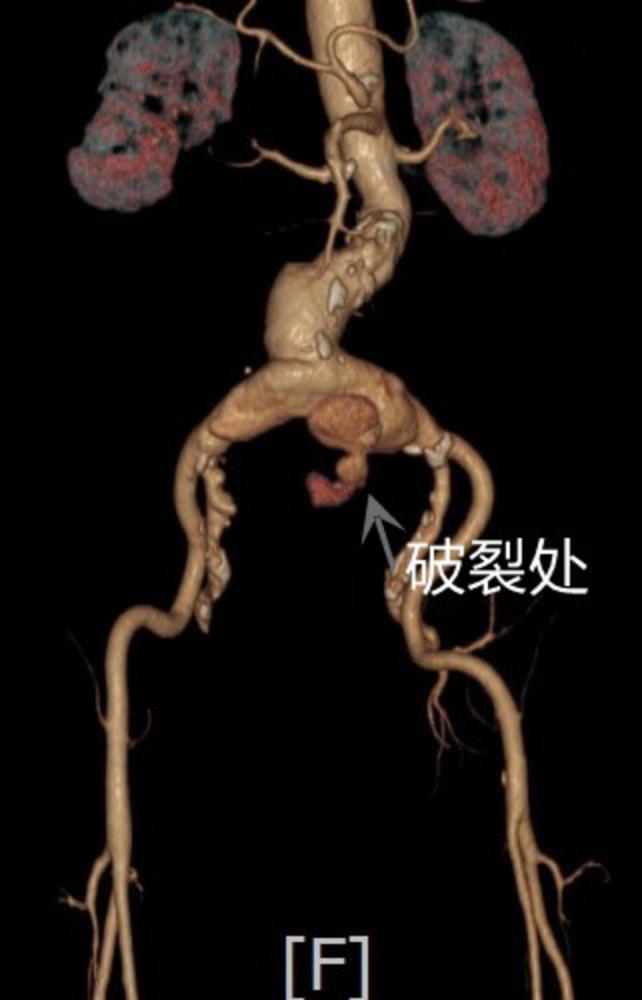

81岁大爷腹部剧痛原来是主髂动脉瘤破裂医生这种病死亡率高达70以上

图片尺寸642x1000